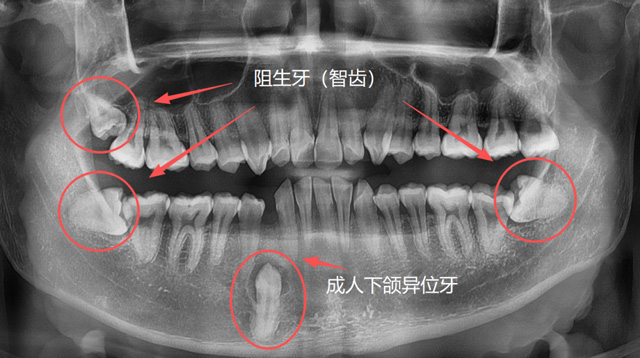

成人异位牙、阻生牙(智齿)

有些人因为牙列拥挤、乳牙滞留或先天发育等原因,恒牙没有在正常的位置萌出,反而往上颌窦、鼻腔等方向生长;称为“异位牙”,还有的牙因为全部或部分埋在了牙槽骨里,无法萌出,称为“阻生牙”,很多智齿就是这样的情况;还有一些超出正常数量的“多生牙”,通常也埋在牙槽骨里无法萌出。

刘伟博士:解剖位置、解剖结构异常的牙齿,拔牙难度更大一些。包括位置异常的阻生牙、异位牙,结构异常的如牙根弯曲、牙根多的牙,还有因为长期慢性炎症造成牙周粘连的牙,以及一些完全退缩到骨头里面的残根,都有一定的难度。